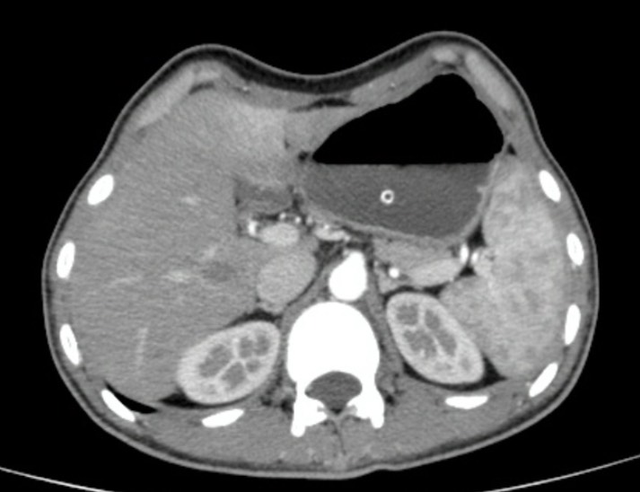

Kết quả chụp CT cho thấy dạ dày bệnh nhân bị giãn rất lớn, sa xuống tận vùng mào chậu – trong khi vị trí bình thường của dạ dày là ở phía trên rốn. Cấu trúc cơ thể bệnh nhân thay đổi rõ rệt, cơ bắp tiêu biến gần như hoàn toàn, bụng hõm sâu theo hình lòng thuyền – dấu hiệu đặc trưng của suy dinh dưỡng mạn tính.

Tình trạng Hẹp môn vị X quang dạ dày.